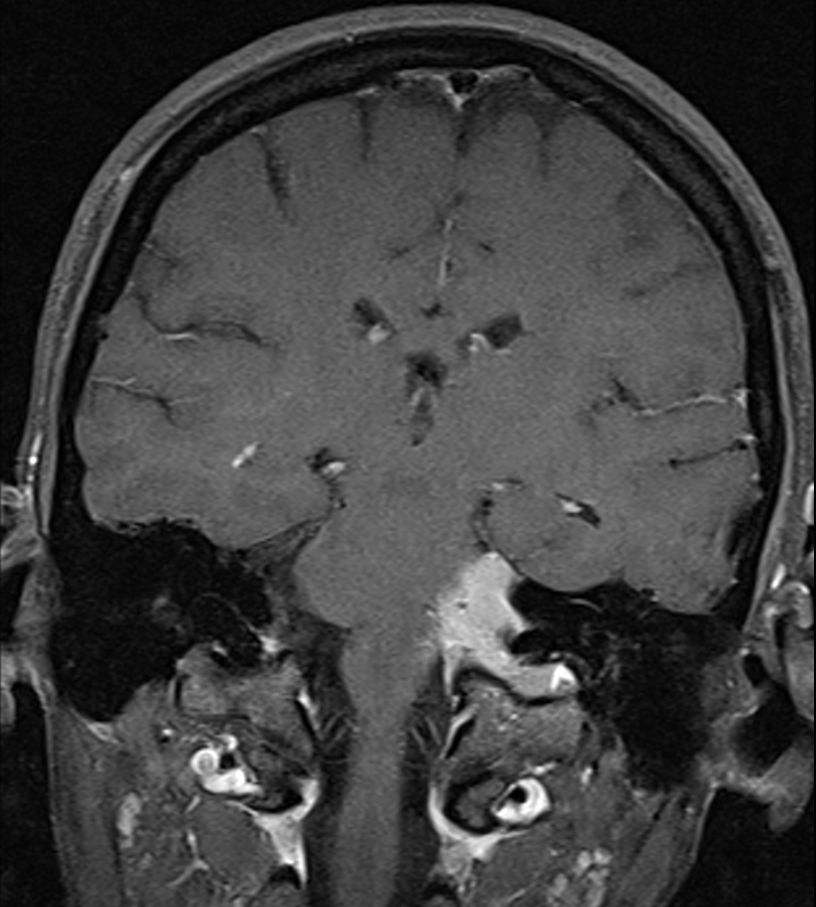

| Meningeom frontal |

59-jähriger Patient, der wegen AV-Block in die Kardiologie eingeliefert wurde. Das CT zeigt einen hirninvasiven Tumor, der die Mittellinie überschreitet. Postoperativ ergab sich ein Meningeom 2. Grades. | . |